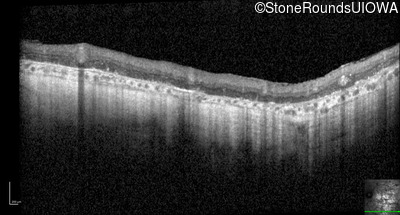

Optical Coherence Tomography - Left - Hand Motion sc

Exemplar / OCT Stack